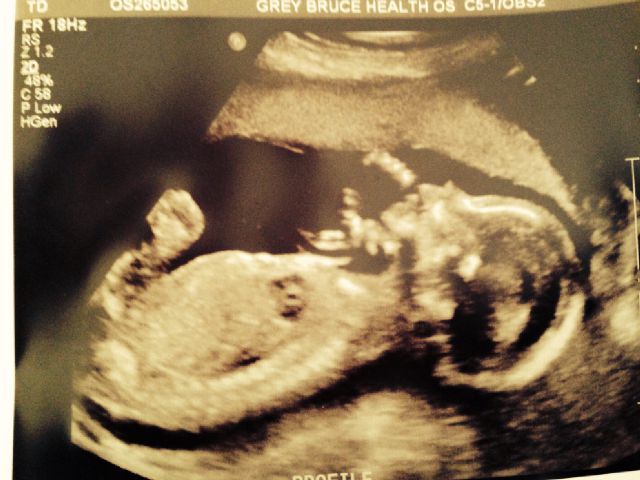

I am not sure what a "true" potty shot is...how is it different from a femur shot? if both legs and bum are imaged and appear to be a "potty shot" can scrotum hide if the gender is a boy? My husband and I saw two legs and the bum with nothing in between..at 19 weeks..but I know she was doing a femur measurement..so is it possible to keep scrotum out of the image when both legs and bum are imaged from what seemed to be underneath? Baby actually measured over 20 weeks and my OB Dr did not see scrotum in the shots either when he reviewed my photos for clues. No penis imaged either.